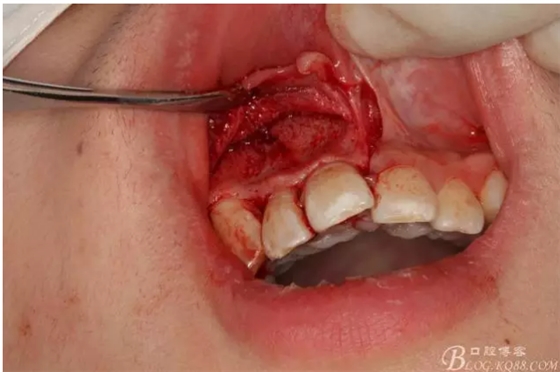

圖2.根管治療術(shù)后直接局部 麻醉下切開(kāi)、翻瓣,發(fā)現(xiàn)12唇側(cè)骨壁有綠豆大小骨缺損